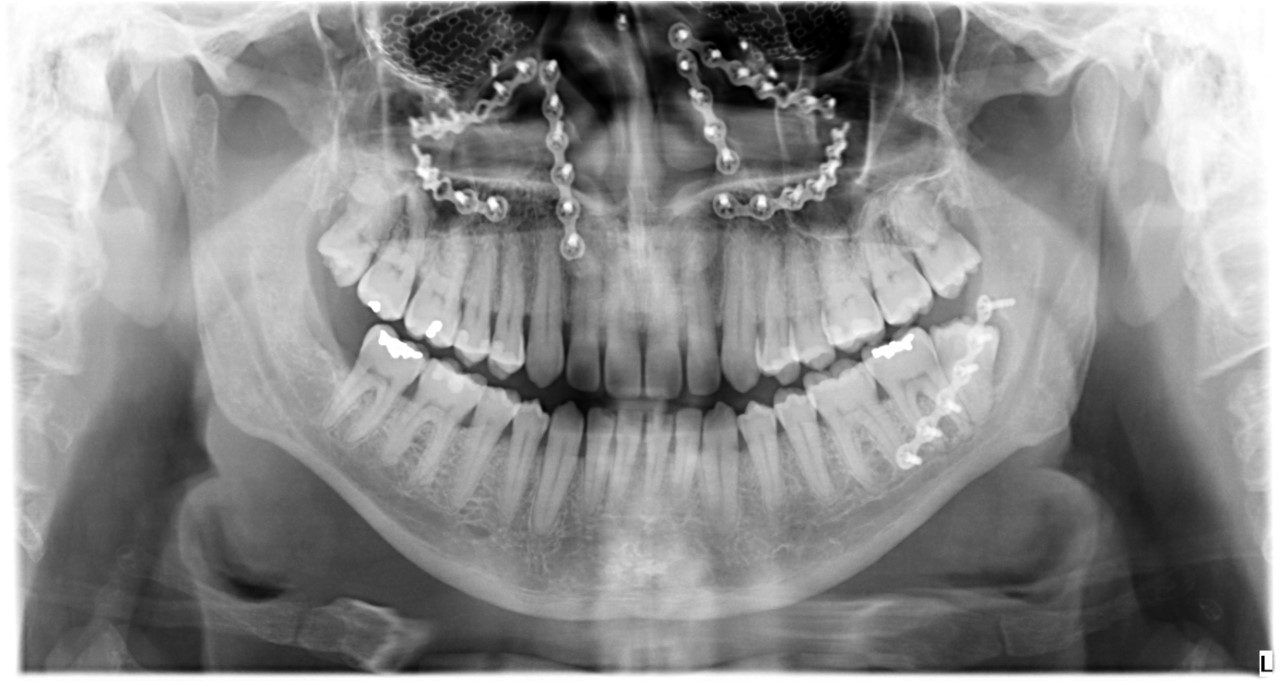

Les spécialistes en chirurgie buccale et maxillo-faciale ont la formation nécessaire pour traiter les patients ayant subi un traumatisme facial. La traumatologie maxillo-faciale comprend tout les types de fractures des os du visage, du front au menton, en incluant les plaies ou lacérations de la peau et des tissus mous, ainsi que les traumatismes dento-alvéolaires.

Les fractures les plus fréquentes sont celles de la mandibule (mâchoire inférieure), celle du tiers moyen du visage (maxillaire supérieur, os malaire, plancher de l’orbite).

La consultation initiale est généralement faite en milieu hospitalier. La chirurgie pour traiter les fractures est faite sous anesthésie générale. Une hospitalisation de courte durée est nécessaire dans la majorité des cas. Les cas plus complexes pourraient nécessiter une période d’hospitalisation plus longue.